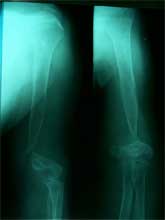

股骨远端骨母细胞瘤        段截肿瘤,大段异体骨移植术后3年愈合良好